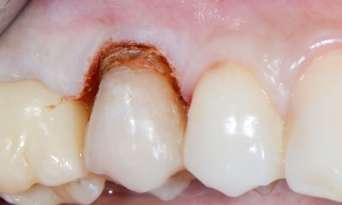

Trattamento di carie cervicale di elemento 1.5 con laser a Erbio

1 2

Paziente femmina, 38 anni che presenta carie cervicale dell’elemento 1.5. Gengivectomia con manipolo angolato, tip in zaffiro con diametro di 400 μm, lunghezza 12 mm, 2.4 W, 20 Hz, 120 mJ E per impulso, potenza di picco 750 W, densità di potenza media 659 W/cm2, densità di potenza di picco 205,860 W/cm2, energia totale 432 J, larghezza impulso 160 μs, distanza tip-tessuto 1 mm, 50% acqua, 50% aria, tempo totale di trafamento 180 sec. Impostazioni dello smalto: manipolo angolato, tip in zaffiro diametro 800 μm, lunghezza 12 mm, totale energia 810 J, ampiezza dell’impulso 160 μs, distanza tip-tessuto 1 mm, 100% acqua, 70% aria, tempo di trafamento totale 180 sec.

Impostazioni dentina e smear layer: tip in zaffiro con diametro 800 μm, lunghezza 12 mm, 3.3 W, 20 Hz, 165 mJ, potenza di picco 1031 W, densità di potenza media 360 W/cm2, densità di potenza di picco 112,346 W/cm2, energia totale 594 J, ampiezza dell’impulso 160 μs, distanza tip-tessuto 1 mm, 100% acqua (18 ml/min), 70% aria, tempo di trafamento totale 120 sec.

Fig. 1 – Cavità su 1.5 Fig. 2 – Particolare della cavità del dente 1.5 Fig. 3 – Preparazione Laser Er:YAG Pluser con lunghezza d’onda di 2940 nm di LAMBDA DoctorSmile, Italia. Fig. 4 – Particolare della cavità dopo gengivectomia Fig. 5 – Particolare della cavità completata dopo la preparazione della dentina Fig. 6 – Restauro finale in composito (Asteria Tokuyama, Japan)